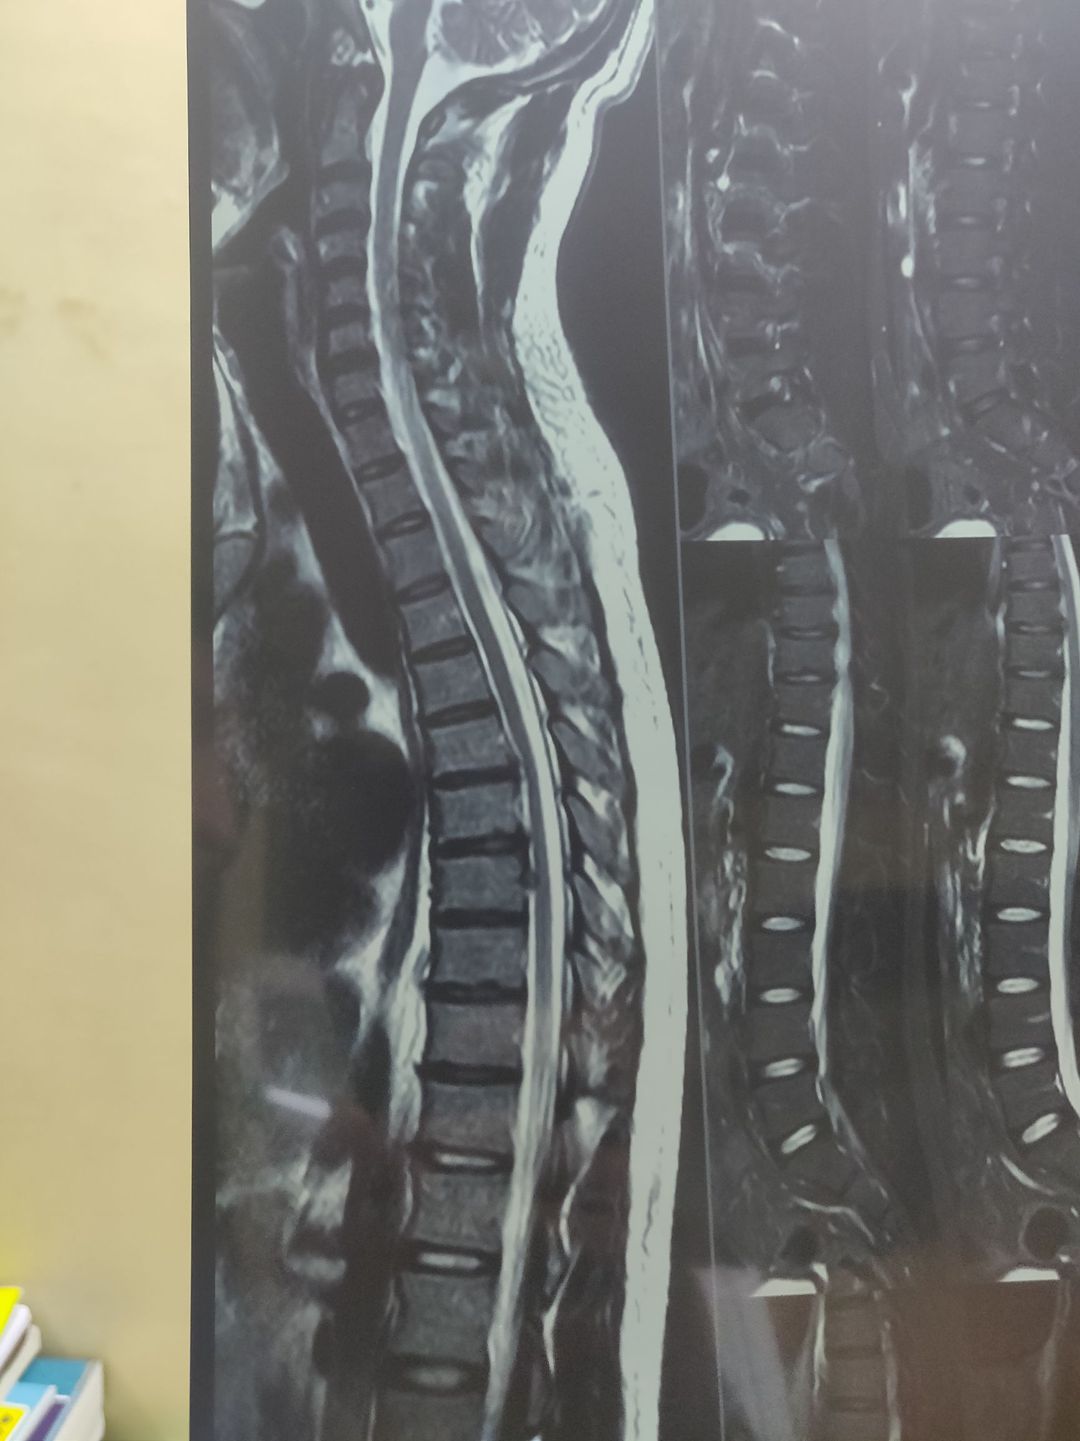

22 year old young male patient , sudden onset sever pain, radiating from upper back to right chest No sensation loss No motor loss Reflerxes are intact No history of trauma What will be possible diagnosis and management? is this disc dulge or disc hernation??